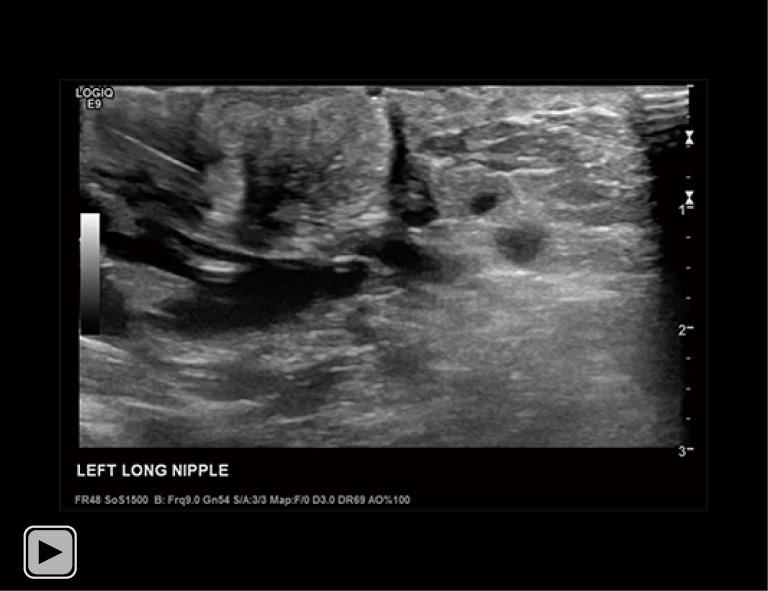

A 34-year-old lactating female presented with a 3-month history of worsening left breast and nipple pain radiating to the left upper outer quadrant, not relieved with conservative therapies. The physical exam revealed a small indentation and a small palpable nodule of the left nipple. There was no associated erythema or redness. Targeted ultrasound and subareolar magnification views revealed findings most consistent with a probably benign inspissated clogged milk duct. Given the patient's history, inability to express milk from the left breast, and plan to lactate for another year, ultrasound-guided aspiration was desired. Post-aspiration images demonstrated complete resolution of the nipple mass. Pathology revealed blood and proteinaceous material, in keeping with the diagnosis of inspissated clogged milk duct. Following the procedure, the patient's symptoms resolved completely.

一名34岁的哺乳期女性,左乳房和乳头疼痛加剧3个月,疼痛放射至左乳房外上象限,保守治疗未能缓解。体格检查发现左乳头有一个小凹陷和一个可触及的小结节。无相关红斑或发红。针对性超声检查和乳晕下放大视图显示的结果最符合可能为良性的浓缩性乳腺管堵塞。鉴于患者的病史、左乳房无法挤出乳汁以及计划再哺乳一年,希望进行超声引导下抽吸。抽吸后的图像显示乳头肿块完全消失。病理检查显示为血液和蛋白质物质,符合浓缩性乳腺管堵塞的诊断。手术后,患者症状完全缓解。